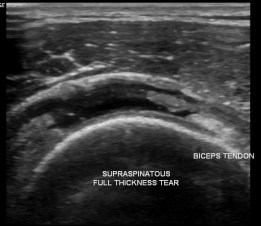

When scanning the shoulder you want to interrogate the biceps tendon, subscapularis, acromioclaivular joint, supraspinatus, glenhumeral joint and posterior labrum.

Supraspinatus Tear